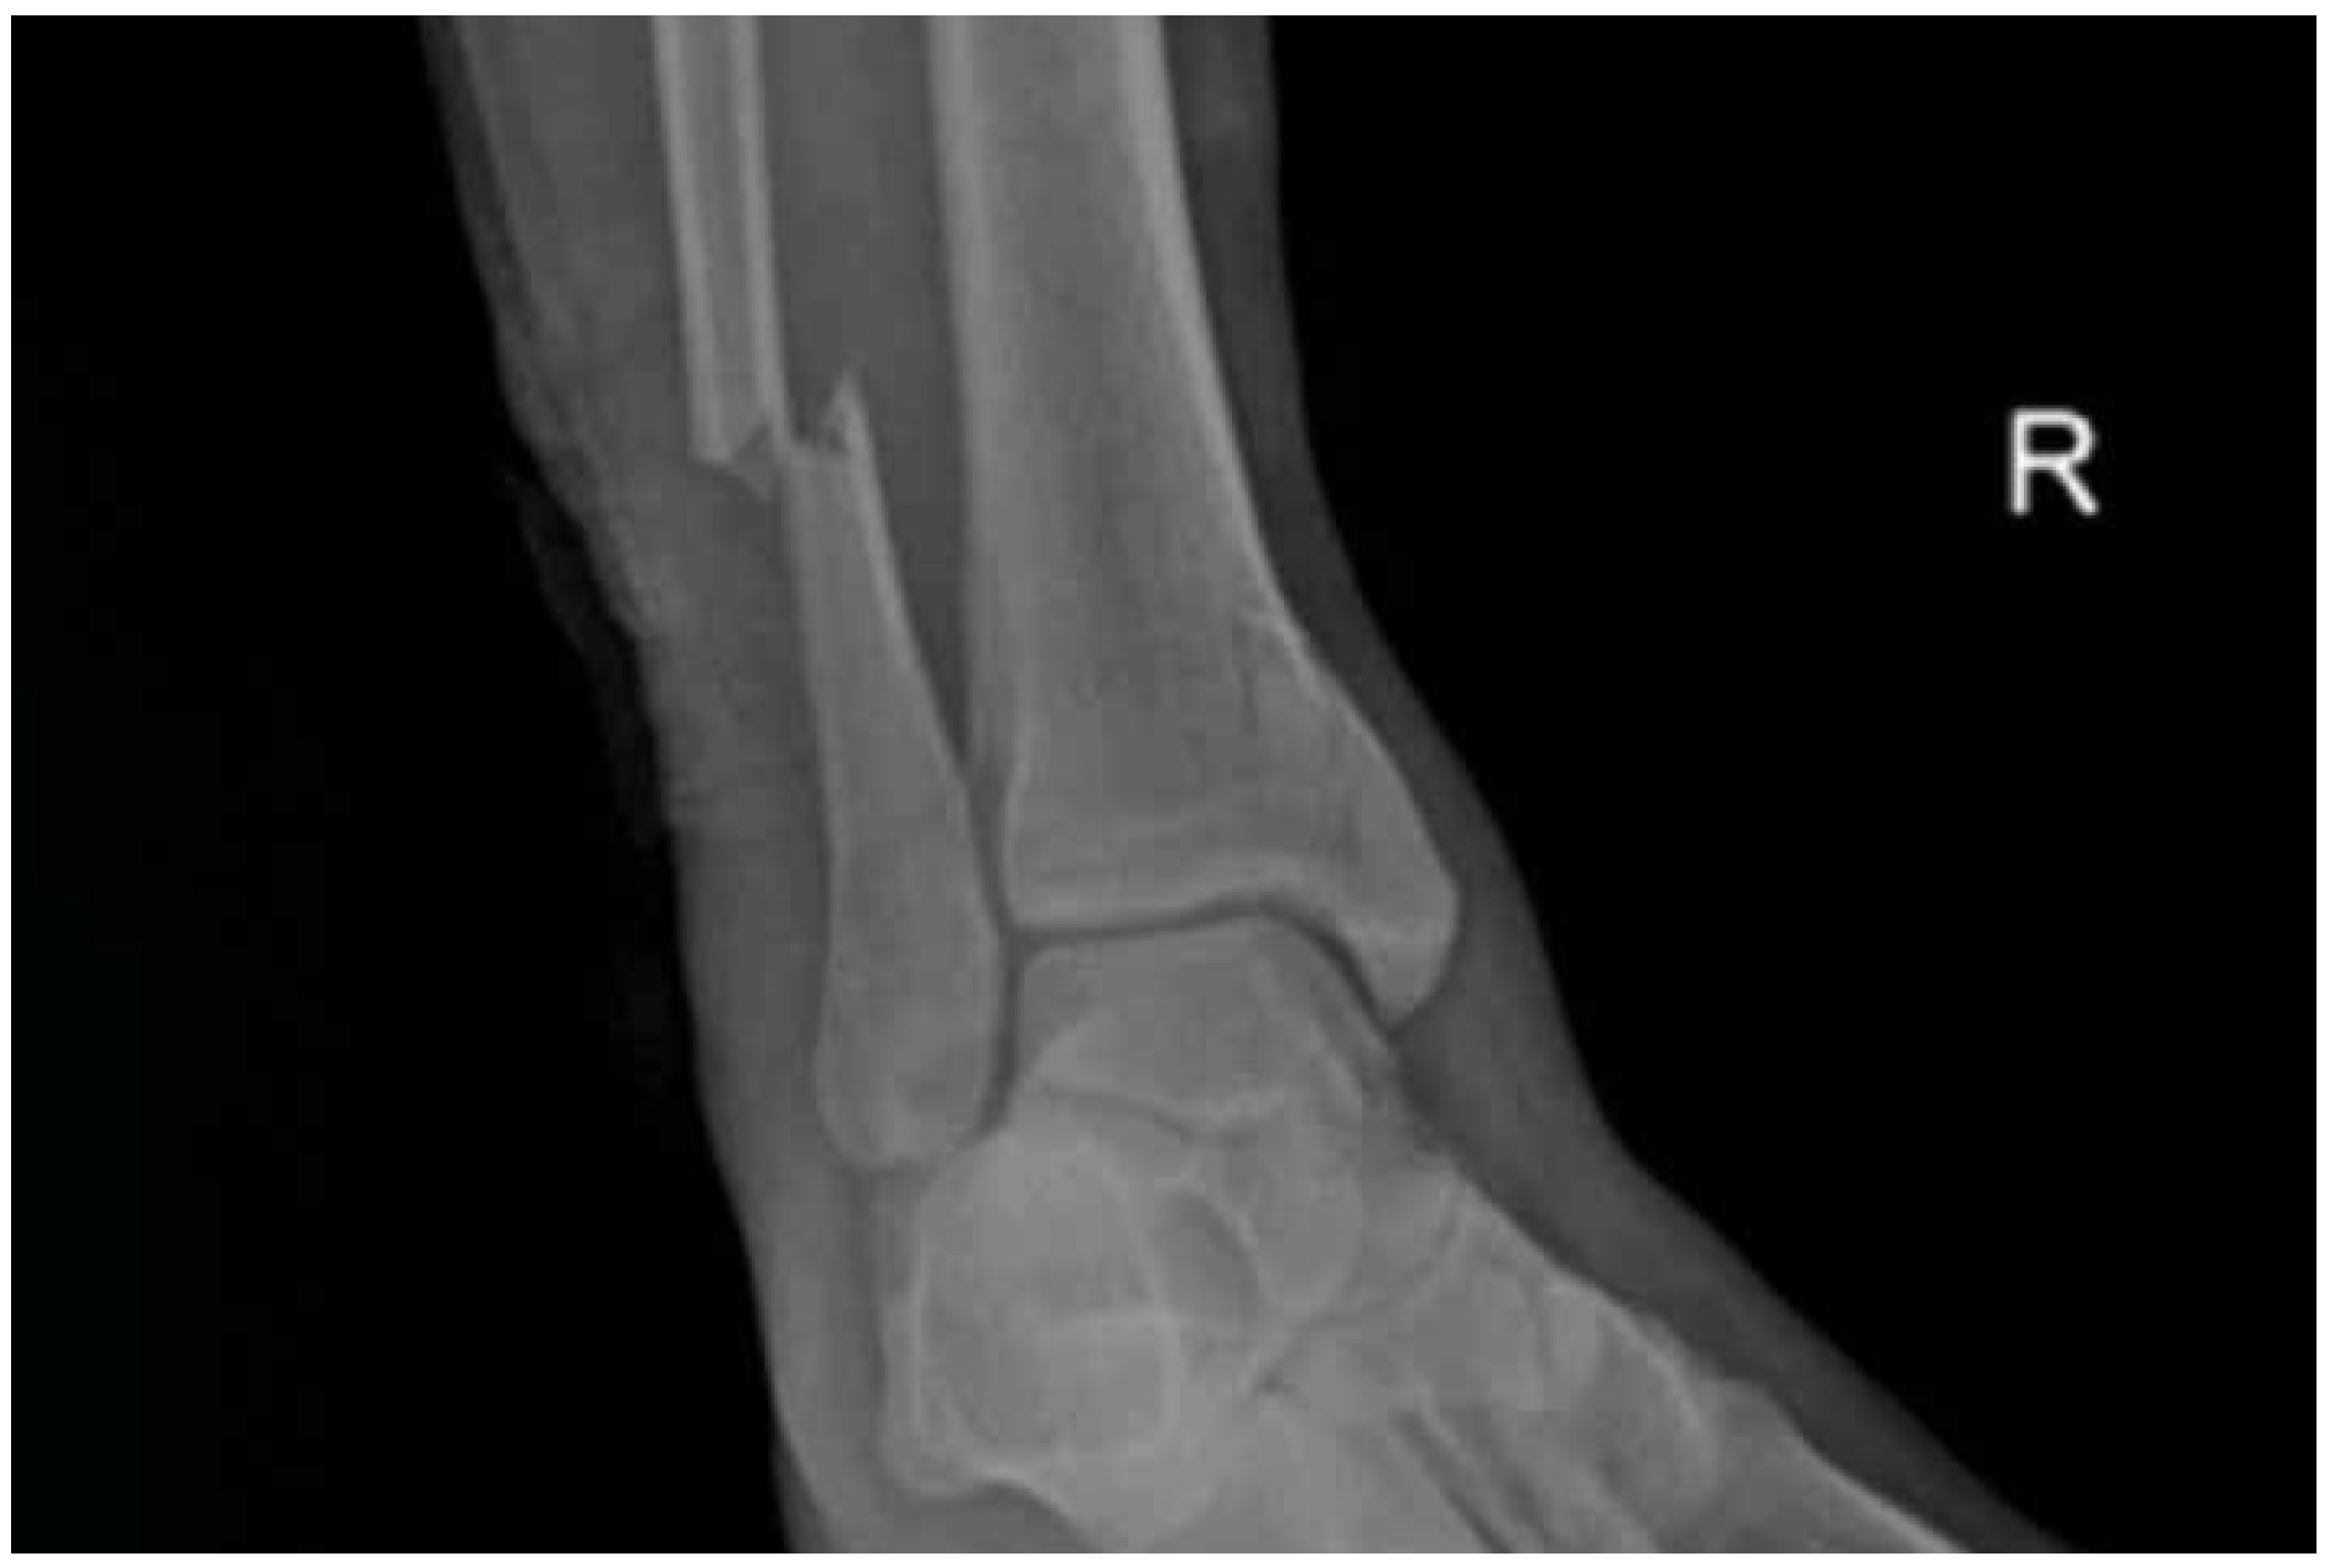

X-ray images were taken on the following day and showed a bimalleolar ankle fracture; vertically oriented non-displaced medial malleolar fracture and supra-syndesmotic lateral malleolus fracture (Figure 2).

Imaging studies play a crucial role in patients with acute Achilles tendon injury both to confirm the diagnosis and to rule out any possible accompanying injuries. The bimalleolar fracture was missed initially in the current patient and was only diagnosed intraoperatively by finding the fracture end of the fibula while exploring the wound for thorough debridement. During the initial procedure, thorough debridement of the wound and Achilles repair was done at the emergency time. Subsequently, an anteroposterior and lateral radiograph of the ipsilateral ankle joint was taken confirming a bimalleolar ankle fracture. Three days later the bimalleolar fracture was fixed on an elective basis and put in a 200 equinus splint. Therefore, the present report shows the importance of routine X-rays in patients with acute traumatic Achilles tendon rupture even if clinical examination confirms complete rupture.

Figure 2. X-ray of the ipsilateral ankle showing associated bimalleolar fracture.